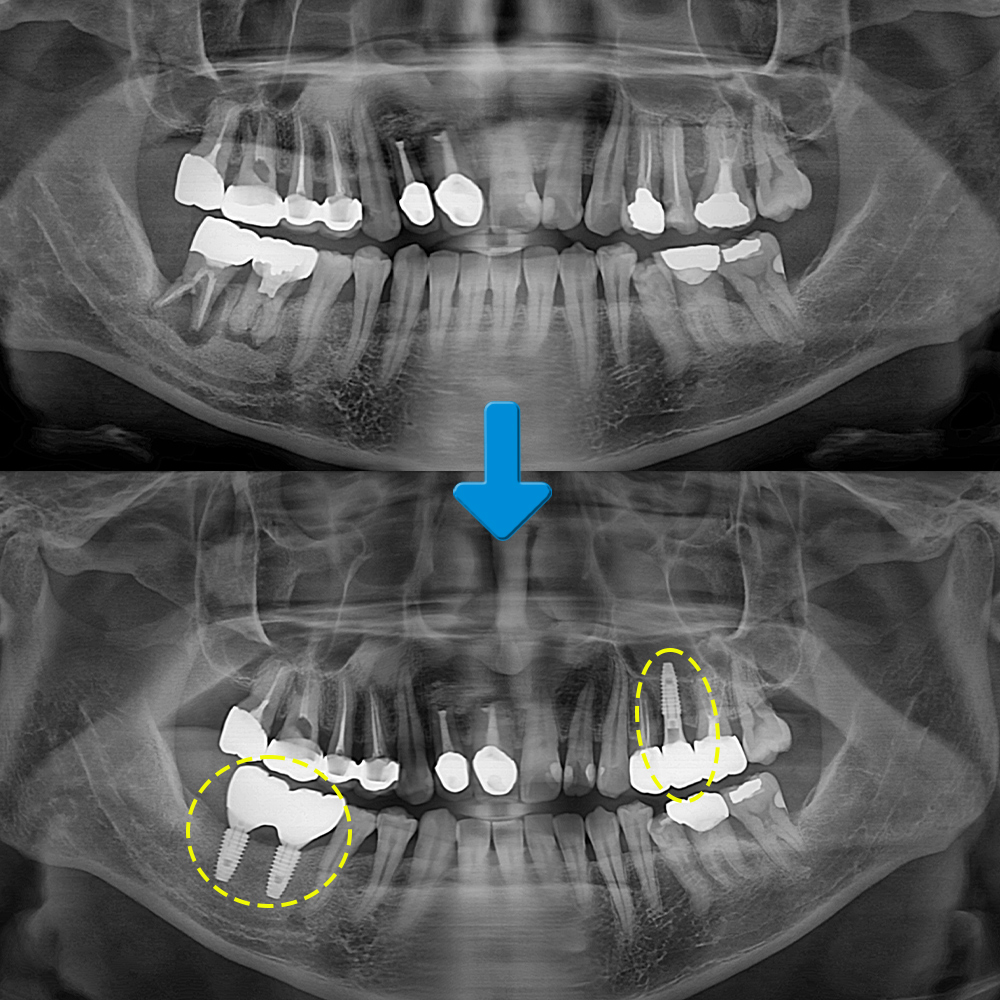

오늘은 가정역치과에서 왼쪽 위 작은 어금니와 오른쪽 아래 큰 어금니 두개 많은 양의 뼈이식과 임플란트를 진행하신 환자분을 소개해 드리도록 하겠습니다.

환자분께서는 오른쪽 아래 어금니가 밥을 먹을 때마다 아프시다며 내원해 주셨는데요. 기존에 신경치료 후 크라운으로 수복되어 있었지만 뿌리에 염증이 심하게 진행되어 잇몸뼈가 많이 녹아 있는 상태였습니다. 추가적으로 왼쪽 위 작은 어금니의 뿌리에도 염증을 확인할 수 있었는데요. 우선 발치 후 소실된 뼈를 이식하여 지켜본 뒤 임플란트 식립을 진행하도록 계획하였습니다.

먼저 원인이 되는 치아를 발치 후 CT 촬영을 진행하였습니다.

이어서 임플란트 식립을 진행하였는데요. 왼쪽 위 작은 어금니는 큰 어려움 없이 최종 보철물까지 마무리하였습니다.

모든 치료를 마친 후의 모습입니다.